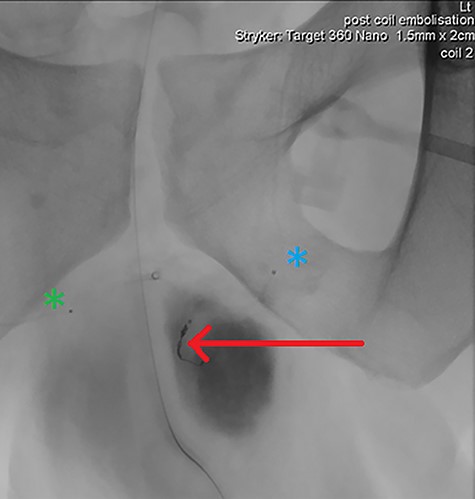

DSA demonstrating significantly reduced flow into the cavernosal artery pseudoaneurysm post-coil embolization (red arrow); note the left (blue asterix) and right (green asterix) distal branches of bilateral internal pudendal arteries for reference.

Final intraoperative fluoroscopic image demonstrating microcoil placement (red arrow); note the microcatheter placement within the left (blue asterix) and right (green asterix) distal branches of bilateral internal pudendal arteries for reference